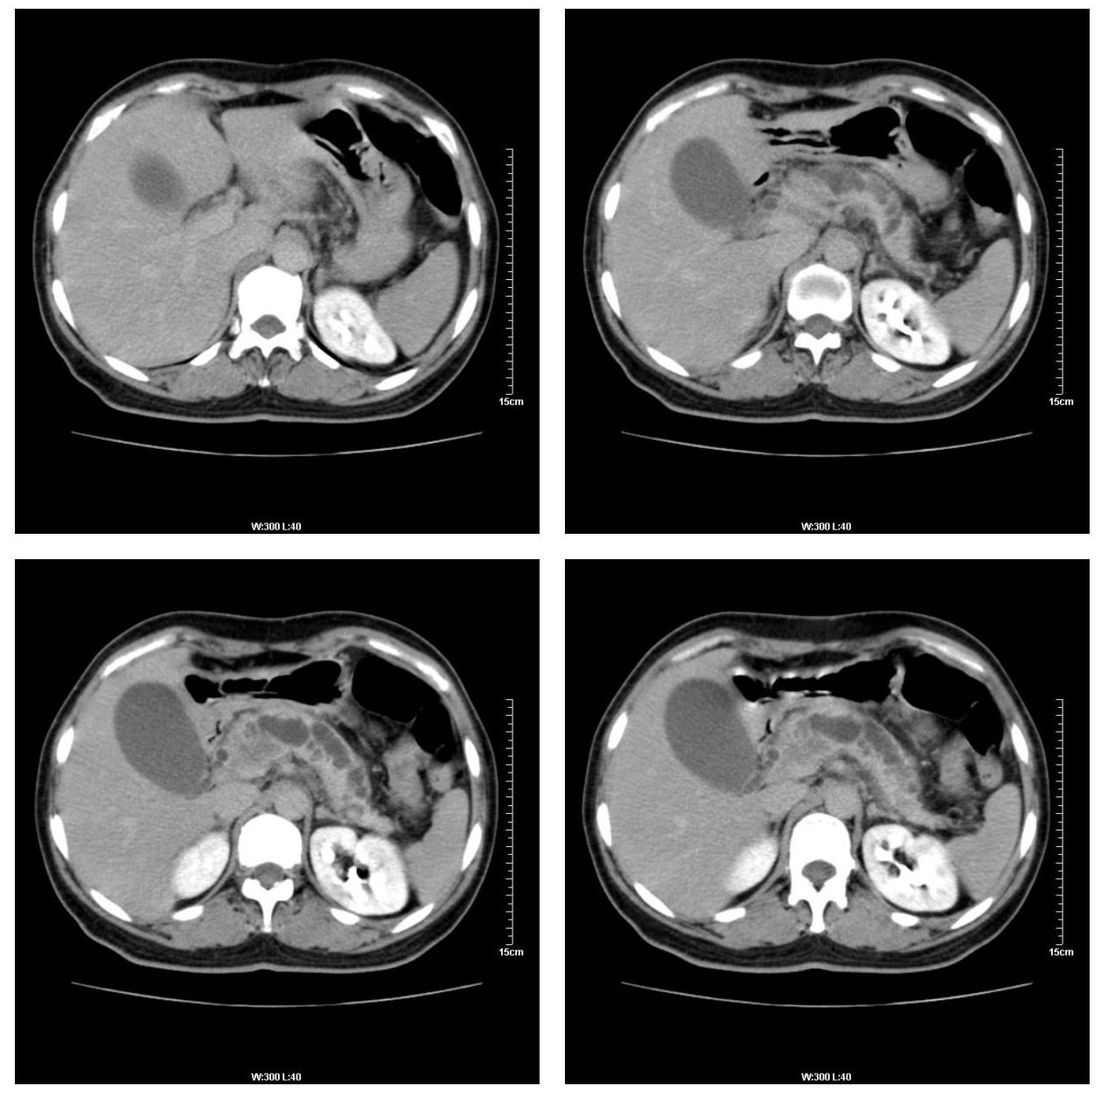

标题: CT13800:女性,52岁。腹痛、腹胀、消瘦及乏力5个月。 [打印本页]

标题: CT13800:女性,52岁。腹痛、腹胀、消瘦及乏力5个月。

慢性胰腺炎、胰腺假囊肿形成,胆总管梗阻,胆囊扩张

胰腺癌可能大

考虑胰头癌

考虑胰腺囊腺癌。

考虑胰头癌可能。

各期时间抓的不太好,门静脉始终显示不佳(门脉瘤栓形成?)。